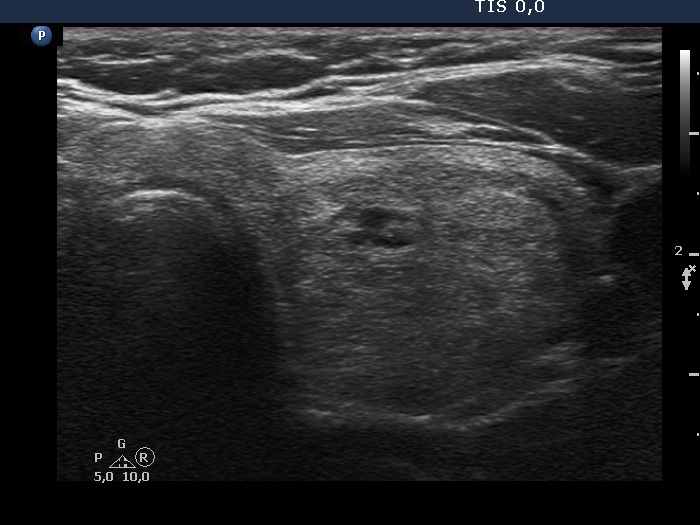

Study on 100 consecutive patients with thyroid nodule - case 067 (ultrasonographic picture 6)

Left lobe, transverse view. There is a minimally hypoechoic-echonormal nodule in the central part of the lobe.